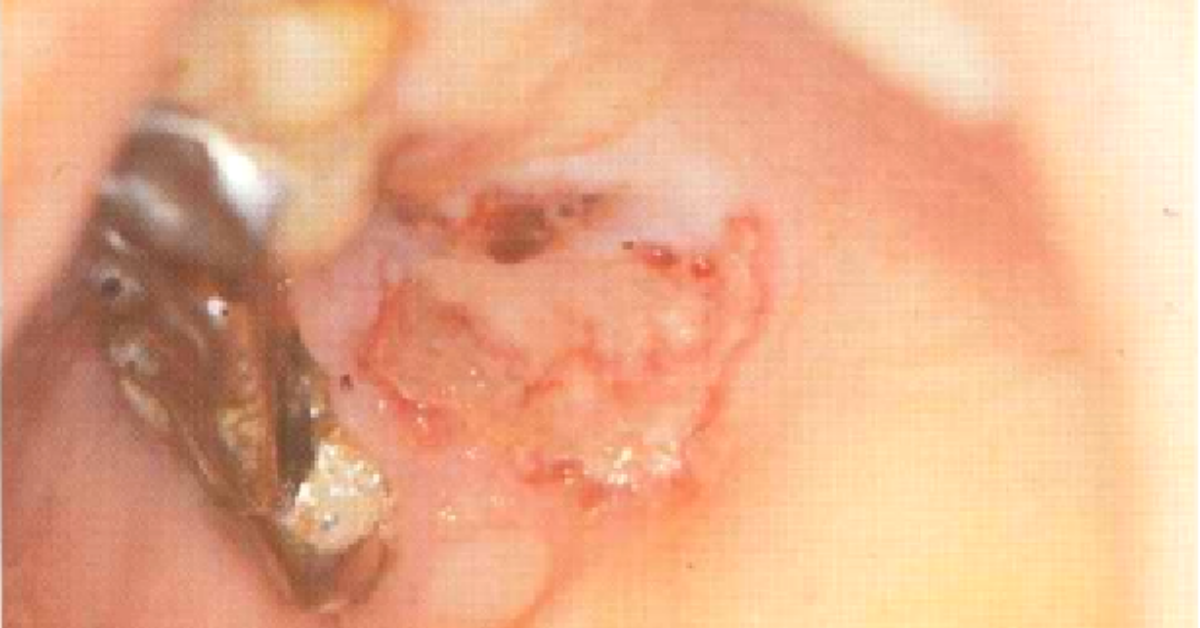

Tumores Metastásicos Las metástasis en los maxilares o la mucosa bucal representan aproximadamente del 1 al 2% de todos los cánceres bucales. La mayoría de ellos se encuentran en las mandíbulas. Las metástasis pueden surgir de carcinomas del tracto gastrointestinal, pulmón, próstata, mama, riñón, etc. Los tumores metastásicos de la mucosa bucal suelen localizarse en lengua, encía y paladar, donde se presentan como nódulos asintomáticos, frecuentemente ulcerados, sin características clínicas específicas. El diagnóstico diferencial incluye granuloma piógeno, granuloma periférico de células gigantes, fibroma, úlcera traumática, carcinoma de células escamosas, etc. Prueba de laboratorio. El diagnóstico se realiza después del examen histopatológico. Puede ser necesaria la investigación del sitio primario de afectación si aún no es evidente. El tratamiento está relacionado con el tipo de neoplasia y la terapia del tumor primario.  Sin embargo,  la quimioterapia es la form...